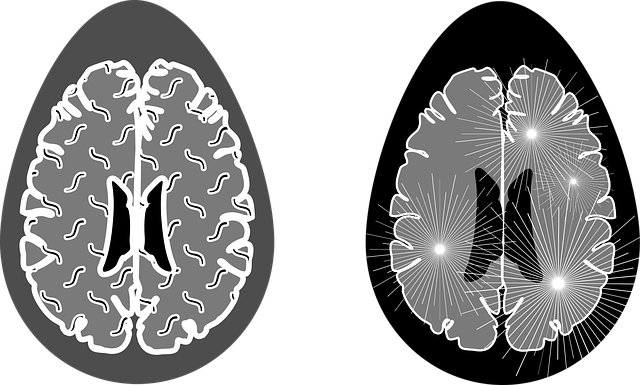

네 세번째 단계까지 오셨다면 높은 확률로 치매일 수 있습니다. 이 검사는 두번째 치매진단검사에서 치매로 진단이 나오면 받아야하는 검사입니다. 병원에서 진행하며 씨티와 엠알아이를 이용하여 뇌영상을 촬영하게됩니다. 엠알아이가 정확도는 높으며 비용은 비싼 편입니다.